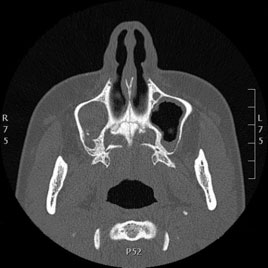

Tomografía computarizada Senos y Estructuras Nasales

Se utiliza para el estudio de los senos paranasales y diferentes estructuras de la fosa nasal.

Ejemplos